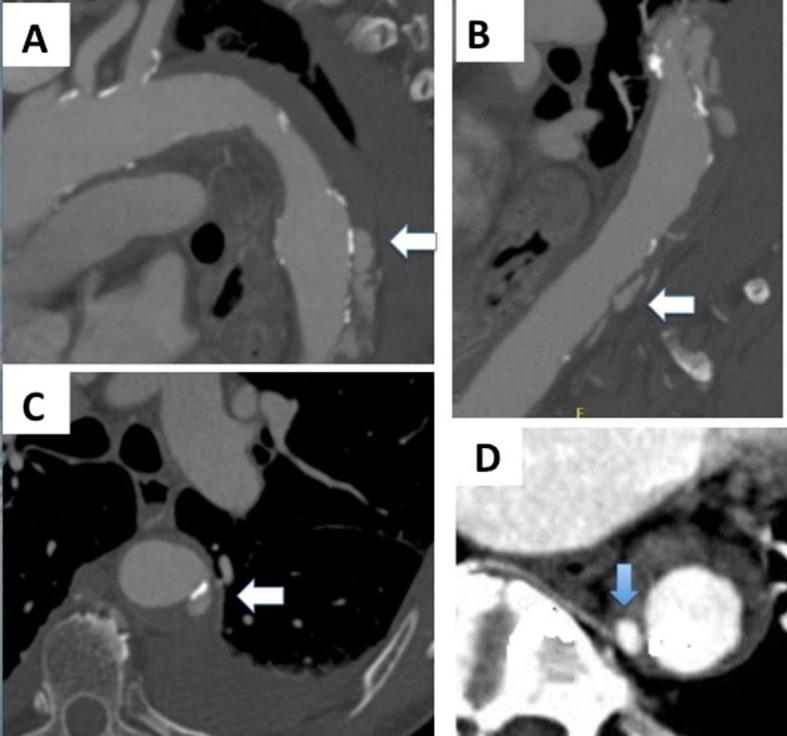

The natural histories of intramural hematoma (IMH) and penetrating atherosclerotic ulcer (PAU) are highly variable as they may progress to aneurysm formation, rupture, or dissection, or even resolve, in the specific case of IMH. Imaging plays an increasingly important role in clinical and surgical management of IMH and PAU. In contrast to ulcer-like projections, images of intramural blood pools have not been widely reported in CT studies of patients with IMH. Understanding the imaging characteristics and the natural course of each of these entities would help clinicians and surgeons to identify patients at greatest risk for bad prognosis and may improve outcomes. This paper discusses the pathophysiology of these entities, the controversies regarding their natural history, and the prognostic factors that should be identified in CT scans.

壁内血肿(IMH)和穿透性动脉粥样硬化溃疡(PAU)的自然病程差异很大,因为它们可能进展为动脉瘤形成、破裂或夹层,甚至在IMH的特定情况下自行消退。影像学在IMH和PAU的临床及手术管理中发挥着越来越重要的作用。与溃疡样突出不同,壁内血池的影像在IMH患者的CT研究中尚未得到广泛报道。了解这些病变各自的影像学特征和自然病程将有助于临床医生和外科医生识别预后不良风险最高的患者,并可能改善治疗结果。本文讨论了这些病变的病理生理学、关于其自然病程的争议以及CT扫描中应识别的预后因素。